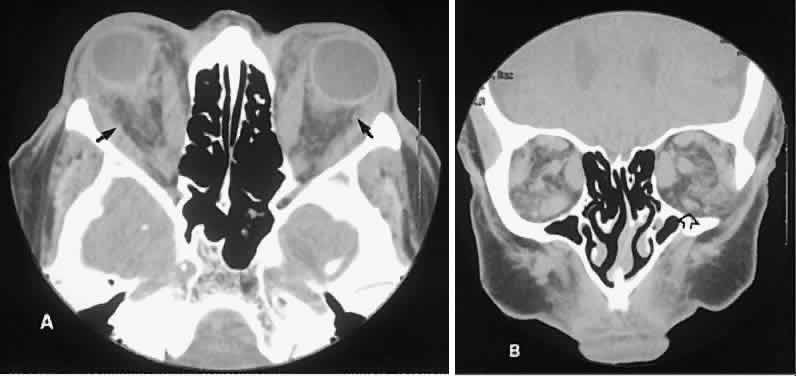

Radiographic evaluation can show either infiltrative or circumscribed masses. Some tumors display a predilection for metastasizing to certain structures, such as prostate carcinoma to bone and cutaneous melanoma to EOMs (Fig. 21). Evidence of bilateral disease at presentation ranges from 7% to 9%, with the prime example being neuroblastoma.71

Fig. 21. A. Axial view shows bilateral involvement from metastatic breast carcinoma. An amorphous infiltrative soft-tissue mass is more apparent in the right orbit, which encases the globe, producing clinical and radiographic enophthalmos. Cutaneous melanoma metastatic to the superior rectus muscle is depicted on axial (B) and coronal (C) views. A locally enhancing and asymmetric enlargement is restricted to the right superior rectus muscle. These features distinguish this lesion from Graves' orbitopathy.